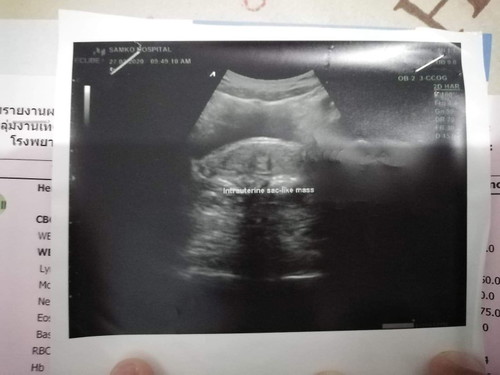

เราซาวตอน6weekเราไม่รุ้ว่าน้องอยุ่ใหนอะค่ะ

ยังไม่เห็นค่ะ หมอว่าไงคะแม่

ไม่ชี้เลยค่ะ รอหมอนัดอีกทีค่ะ